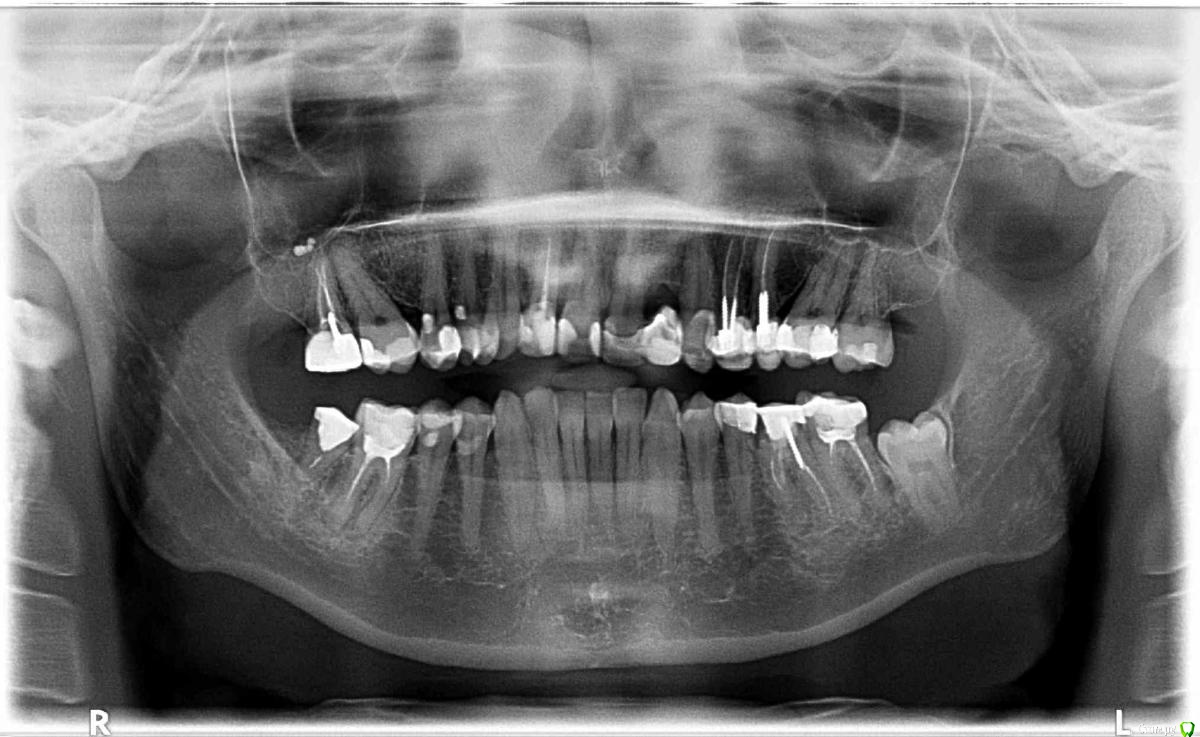

ElenaP. Опубликовано 17 августа, 2018 Поделиться Опубликовано 17 августа, 2018 Уважаемые доктора и специалисты! Помогите, пожалуйста, разобраться, что произошло с моими верхними зубами после установки цельного моста из 8 зубов. 1. Почему ширина всего зубного ряда уменьшилась на почти на 1,5 см, снимок "после" был сделан на той же машине, что и "до". 2. Почему провисло "небо" слева, что это означает? 3. Что за треугольники на снимке "после" в уголках верхней челюсти, похожие на разрез челюсти? Простите, если мои вопросы непрофессиональные, мой доктор считает, что все хорошо, хотя мост пришлось снять из-за сильнейших болей в лице и во рту, разумеется. Прошло более 5 месяцев, до сих пор хожу с временными мостами, но все страшно болит. Спасибо большое. На всякий случай даю снимок оригинальный, до того, как решилась на это безумие. Ссылка на комментарий

kramer Опубликовано 17 августа, 2018 Поделиться Опубликовано 17 августа, 2018 (изменено) 1. Ничего не изменилось. На снимке №2 и 3 в фокус попал еще позвоночный столб, поэтому объекты на снимке №1 кажутся больше. 2. ??? 3. Укажите стрелкой. Изменено 17 августа, 2018 пользователем kramer Ссылка на комментарий

Бендер Опубликовано 17 августа, 2018 Поделиться Опубликовано 17 августа, 2018 Нижний ряд тоже получается ушёл на полтора сантима? Ссылка на комментарий